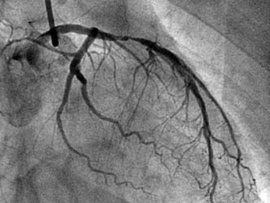

心臟造影就是經過血管插入一隻導管到冠脈部位,然後打入造影劑,然後做拍片或者透視。當然,造影是有一定風險的,但現在積累了很多經驗,風險已經很小了,但還是要患者自己權衡是不是要做。